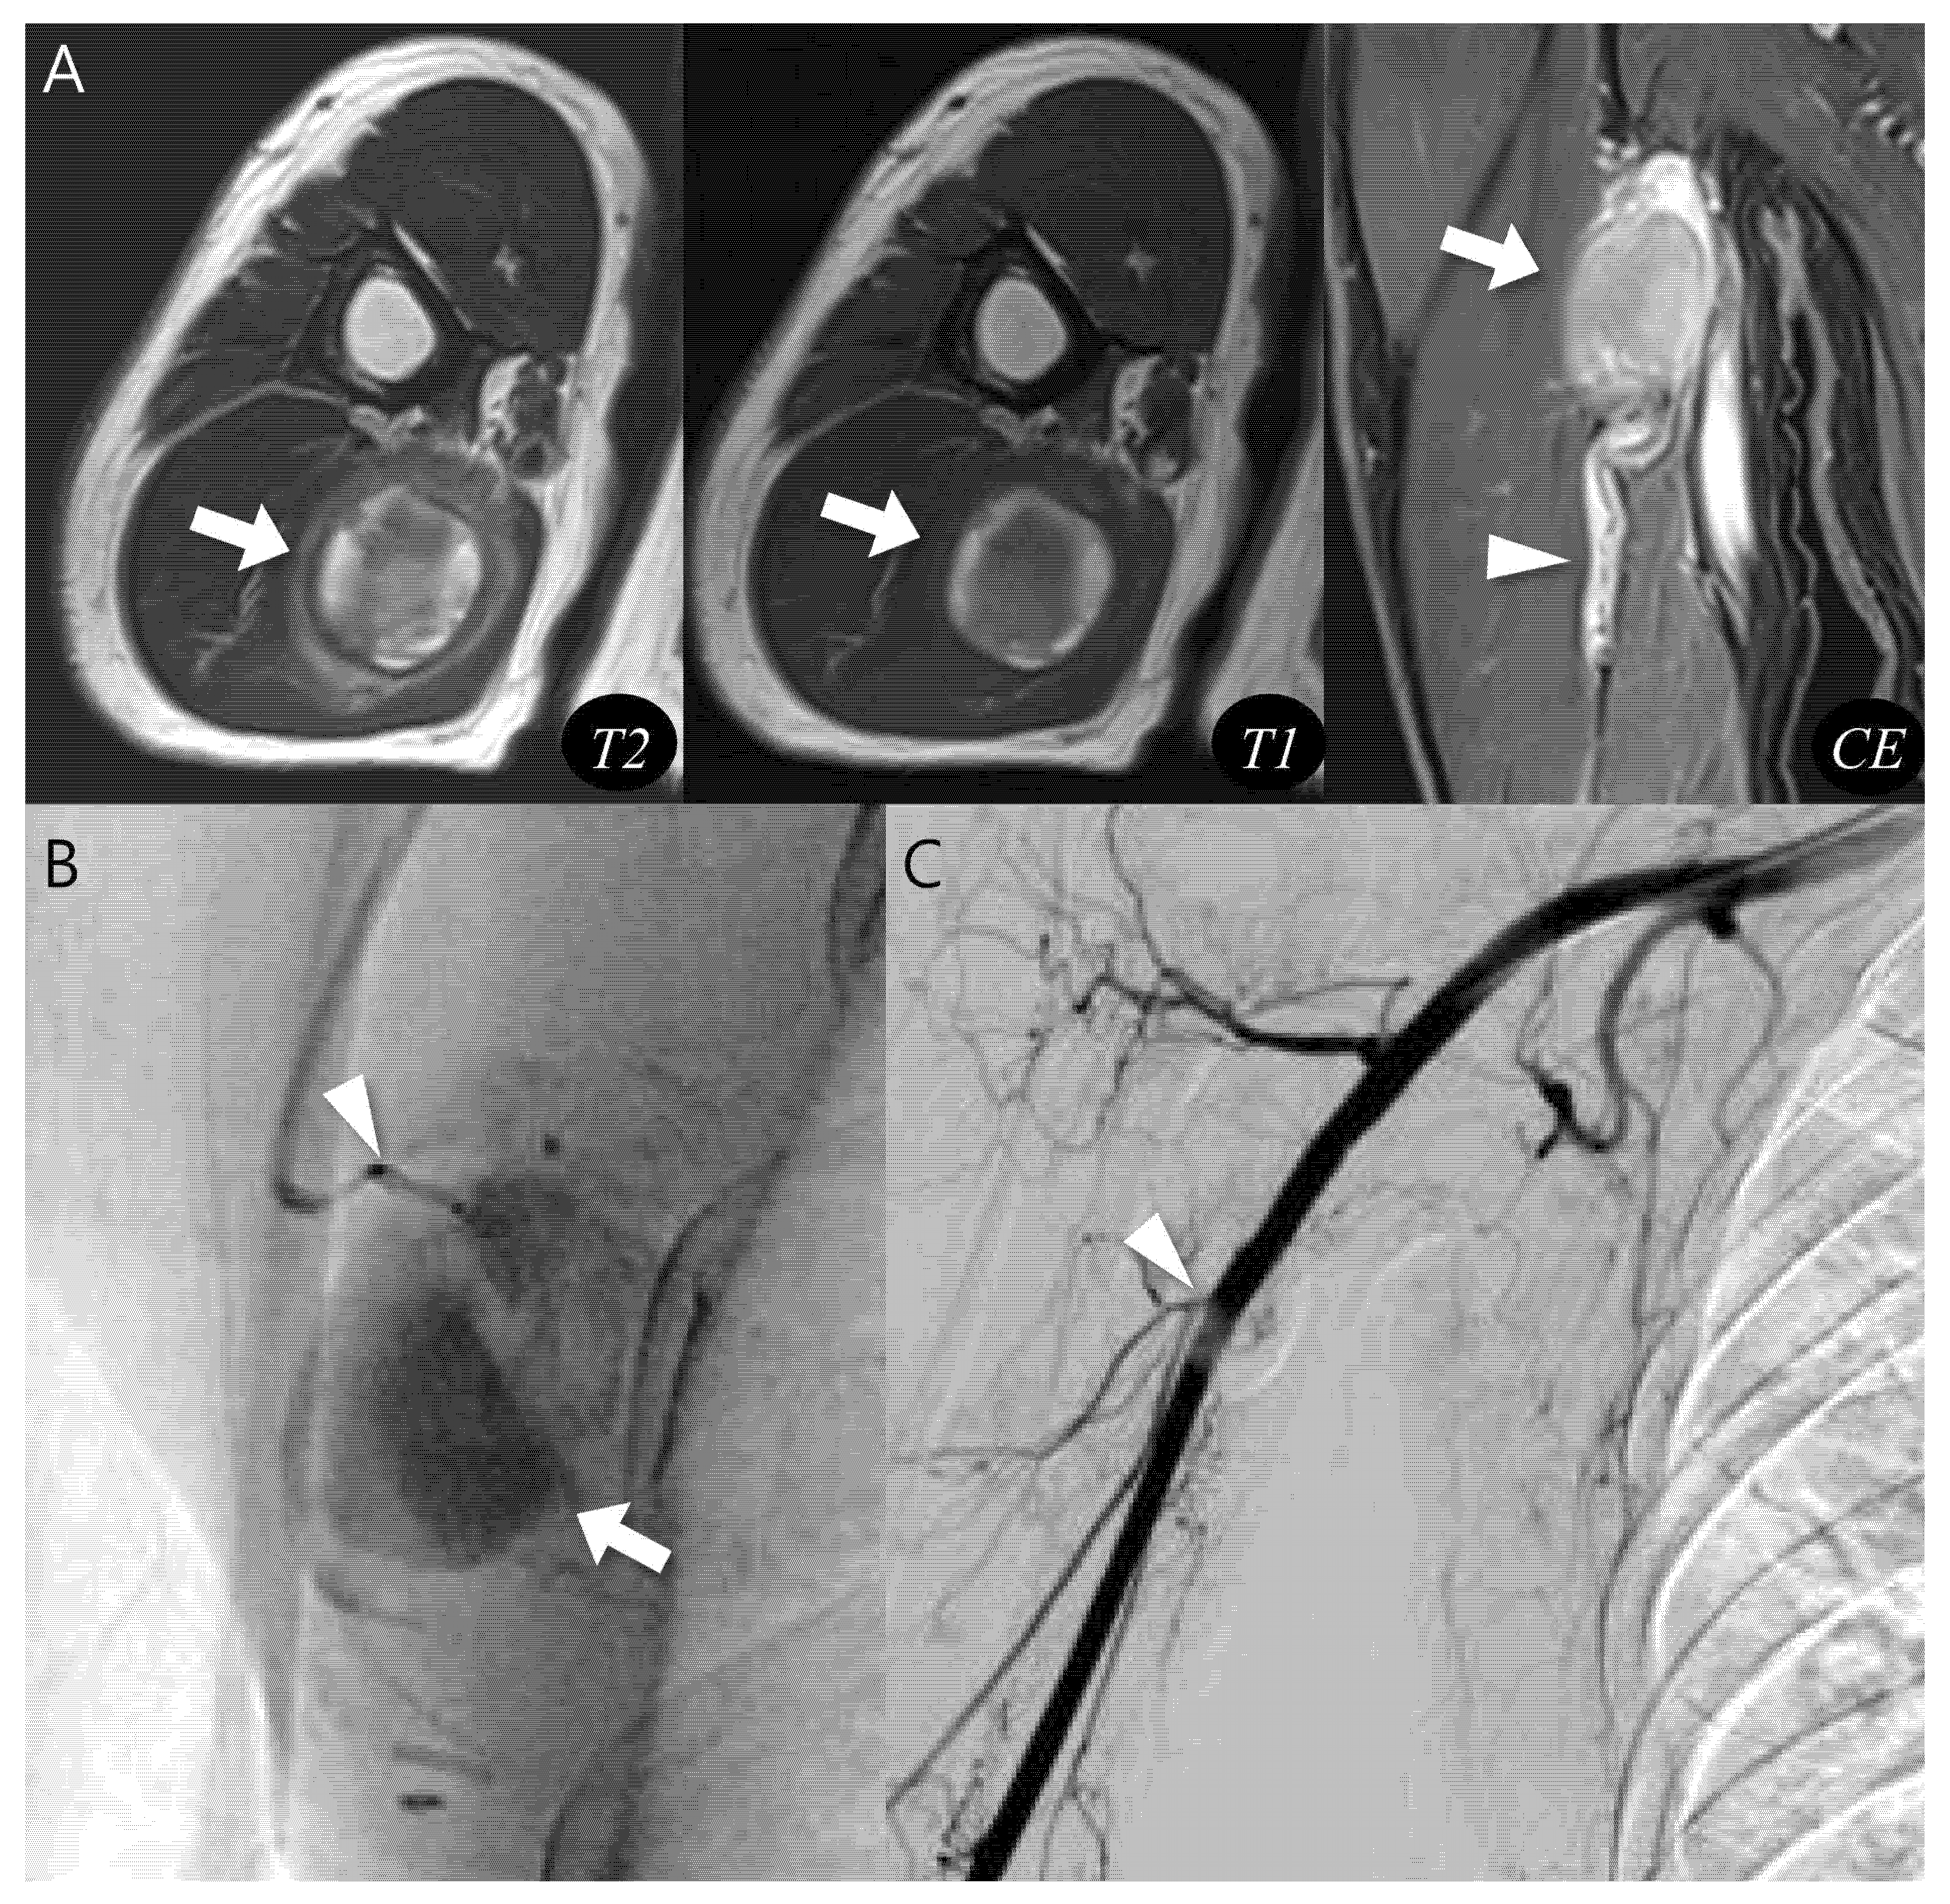

Figure 3.

Diagnosis and treatment of pseudoaneurysm. (A) Axial T2-weighted, T1-weighted, and coronal T1-weighted contrast-enhanced MR images show an intramuscular, ovoid lesions (arrow) in the upper arm. The lesion demonstrates a central flow void with inner peripheral high SI on T1-weighted image (arrow, mural thrombus) with neurovascular involvement (arrowhead). (B) Digital subtraction angiography reveals a pseudoaneurysm sac (arrow) with a narrow neck arising from the brachial artery (arrowhead). (C) Post-embolization angiography demonstrates successful occlusion of the pseudoaneurysm neck (arrowhead).

In the last pseudoaneurysm case (Figure 5), typical MRI findings, such as a central flow void was equivocal and inner peripheral high SI on T1WI was absent, making the diagnosis more challenging. Instead, the presence of neurovascular bundle involvement raised strong suspicion for pseudoaneurysm which was subsequently confirmed by complementary vascular imaging. This case demonstrates that the diagnostic flowchart retains its clinical value even in atypical presentations, underscoring the importance of integrating ancillary features such as neurovascular involvement to achieve accurate diagnosis and ensure appropriate treatment.

Figure 5.

Pseudoaneurysm with neurovascular bundle involvement diagnosed without biopsy. (A) Axial T2-weighted and T1-weighted MR images demonstrate a hematoma-like lesions (thin arrows) with equivocal central flow void or absent inner peripheral high SI. However, neurovascular bundle involvement (thick arrow) in sagittal T1-weighted contrast-enhanced MR image raises suspicion for pseudoaneurysm. (B) Doppler ultrasonography reveals a characteristic “Yin-yang” sign with neck at the brachial artery (arrow), confirming a “to-and-fro” flow pattern. (C) CT angiography with 3D reconstruction demonstrates a pseudoaneurysm arising from the brachial artery, consistent with the MRI suspicion. This case highlights that recognition of distinct MRI features can guide appropriate diagnosis without unnecessary biopsy.